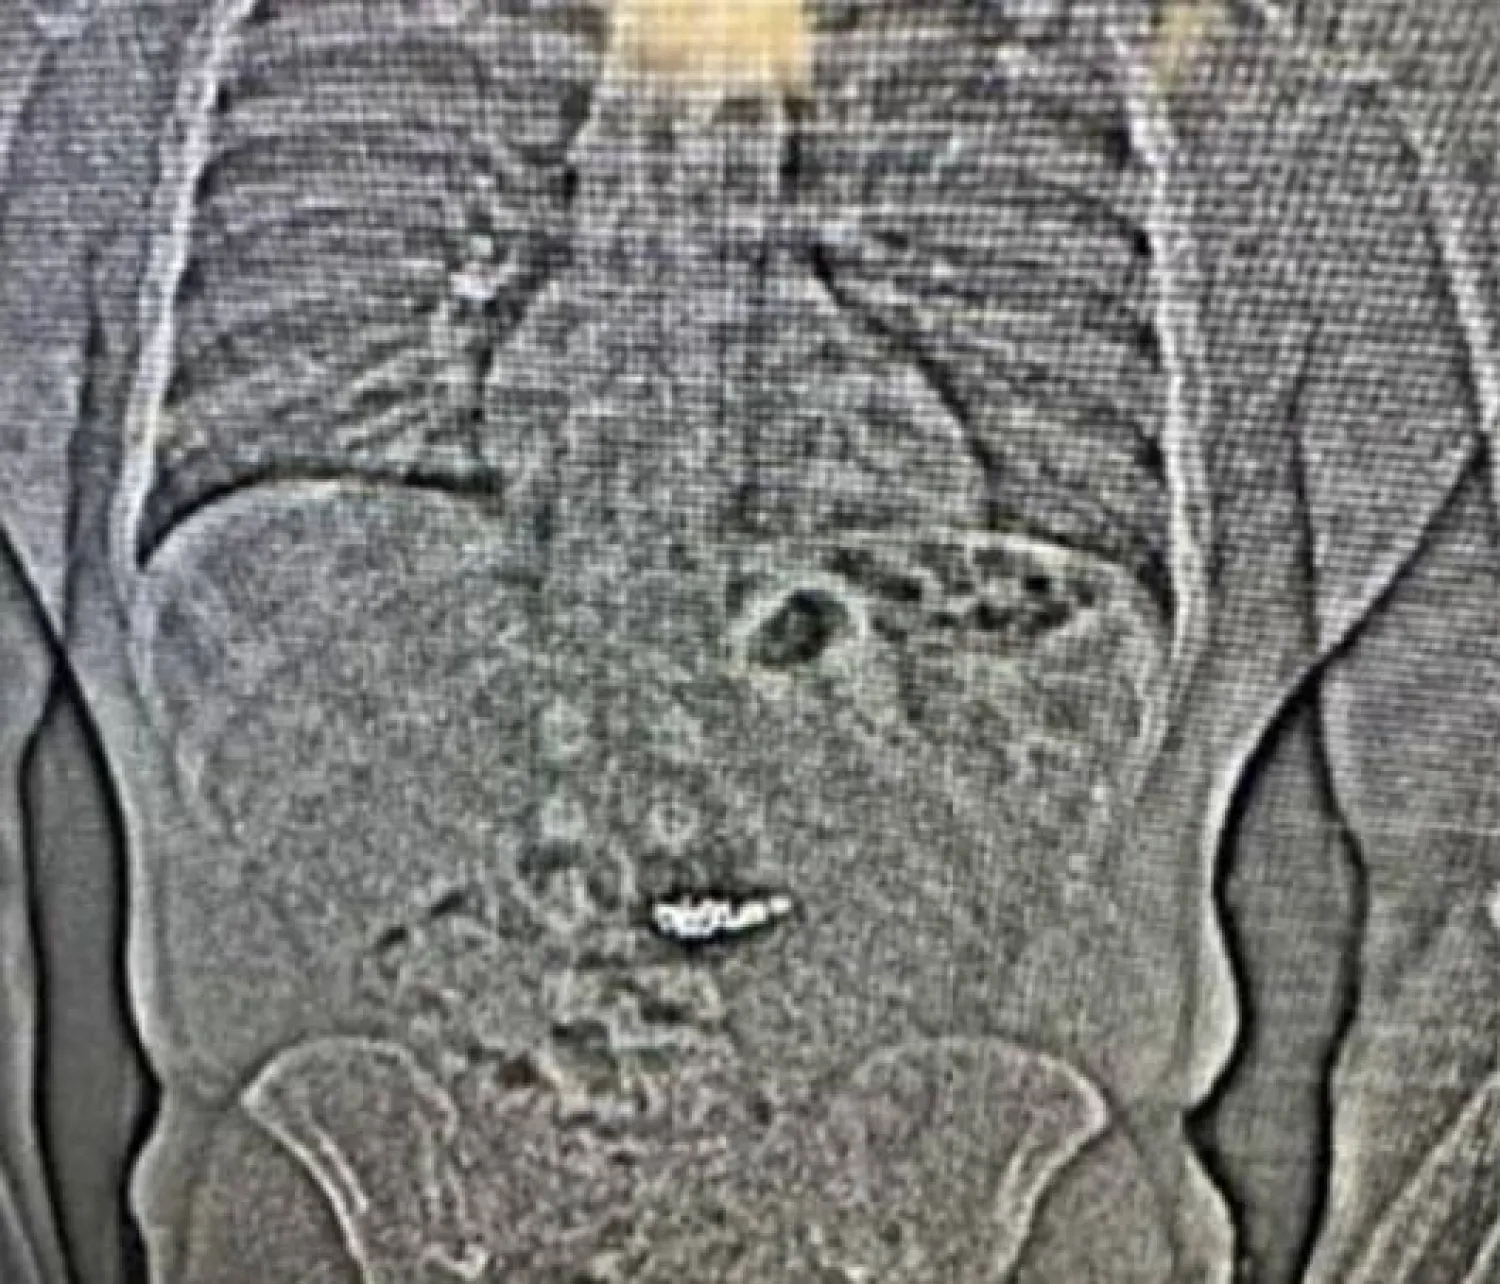

وأفادت الشرطة بأنه أثناء فحص المشتبه به في سجن مقاطعة واشنطن، تم العثور على «أجسام غريبة في معدته».

وأضاف البيان: «يُشتبه في أن هذه الأجسام الغريبة هي أقراط (تيفاني آند كو) التي سُرقت، ولكن يجب جمعها... بعد مرورها عبر نظام جيلدر».